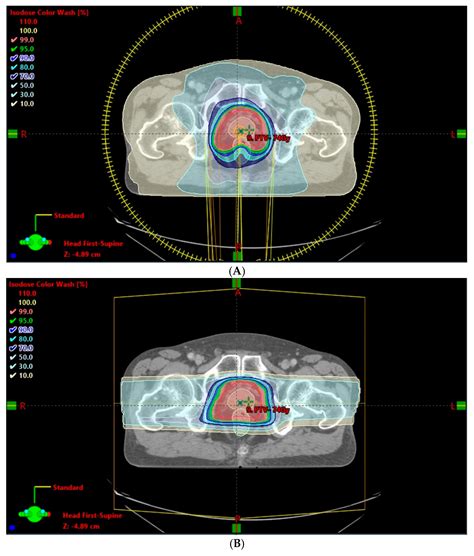

At its core, Prostate Cancer Radiation Therapy is designed to precisely target the prostate gland while sparing the surrounding healthy tissues, such as the bladder and the rectum. The success of this treatment lies in its ability to deliver concentrated doses of radiation specifically to the malignant cells. Over time, these cells lose their ability to divide and grow, eventually dying and being naturally cleared away by the body’s immune system.

The journey of Prostate Cancer Radiation Therapy begins with a “simulation” or planning session. During this stage, your medical team will use CT or MRI scans to map the exact location of your prostate. This mapping is critical because it ensures the radiation is delivered with millimeter precision.

Modern advancements have significantly improved the safety profile of Prostate Cancer Radiation Therapy. Techniques such as Image-Guided Radiation Therapy (IGRT) allow doctors to visualize the prostate’s position in real-time just before the radiation is delivered. This accounts for minor movements caused by breathing or changes in bladder volume, ensuring the radiation remains locked on the target throughout the session.